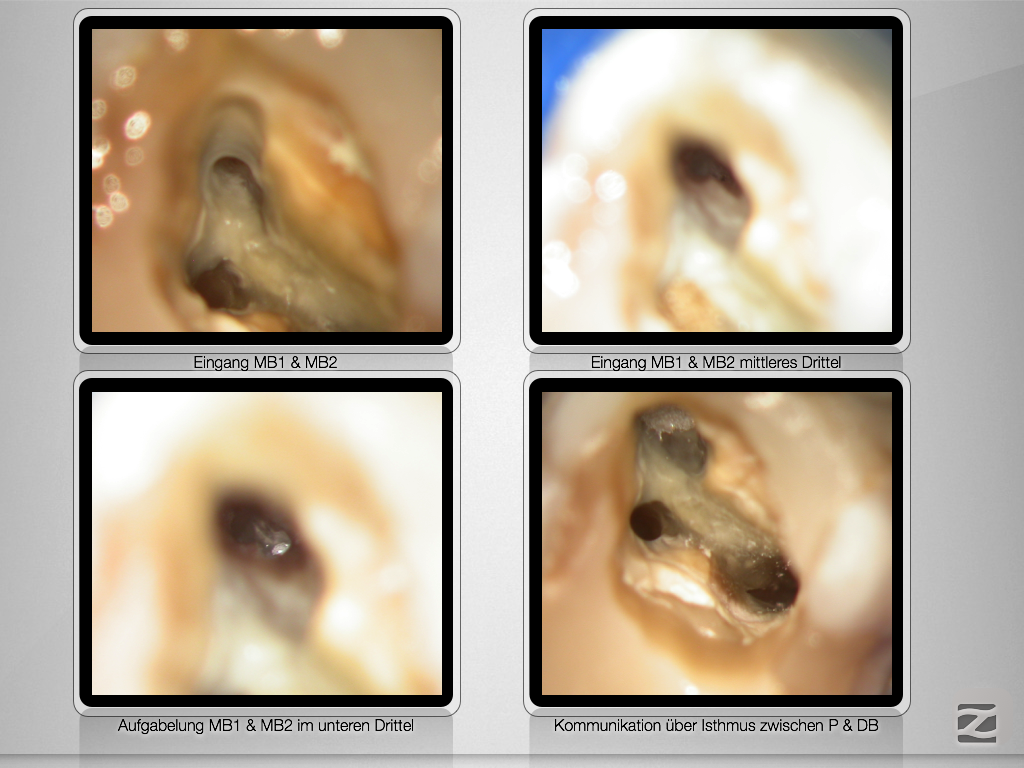

Navigierte Aufbereitung